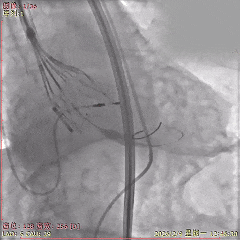

术中影像

初始造影确定无冠窦

瓣膜稳定释放至全展开

展开后造影,瓣膜位置可

多角度评估,确认瓣膜稳定

瓣膜脱钩后,无位移

最终造影,瓣膜位置可,无瓣周漏